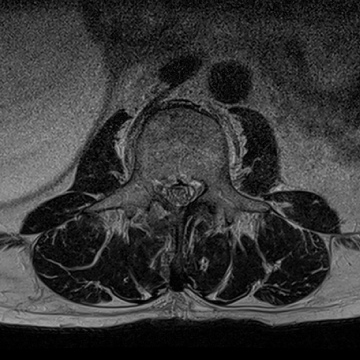

허리 디스크 수술 전·후

2022.08.01

2022.08.04